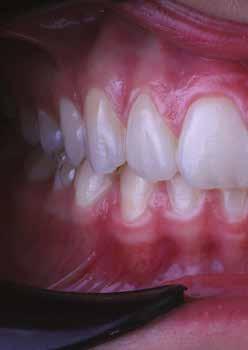

Egy 34 éves páciens esztétikai problémával érkezett. A természetesen keskeny metszőfogak miatt kisebb diasztémák és fekete háromszögek voltak láthatók a front régióban. A rések korábban kompozittal történő zárása már megtörtént, azonban az eredmény nem felelt meg az elvárásoknak (1. ábra). A fekete háromszögek továbbra is láthatóak voltak, és a kompozitanyag jól kivehetően helyezkedett el a fogak felszínén. A 11-es és 21-es fogak szélessége között aszimmetria mutatkozott, a korábbi restaurációk nehezen tisztíthatók voltak, és gyorsan elszíneződtek (2. ábra). A frontfogak palatinális felszínén retenciós drót volt rögzítve, a 11-es és 21-es fogak pedig kompozittal történő sínnel voltak összekötve (3. ábra). Bármilyen további kezelés során a retenciós drót eltávolítása szükséges, mivel az akadályozza a megfelelő approximális restaurációk kivitelezését. Az első konzultáció során teljes fotódokumentáció készült. Egy gyors kompozit mock-up segítségével bemutatásra kerültek a lehetséges esztétikai eredmények. A kezelési terv elfogadását követően időpont egyeztetésre került sor a beavatkozás elvégzésére.

1. ábra: A mosolyról készült fénykép a kezdeti vizsgálat során.